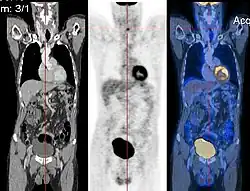

Image registration is a process that searches for the correct alignment of images.[21][22][23][24] In the simplest case, two images are aligned. Typically, one image is treated as the target image and the other is treated as a source image; the source image is transformed to match the target image. The optimization procedure updates the transformation of the source image based on a similarity value that evaluates the current quality of the alignment. This iterative procedure is repeated until a (local) optimum is found. An example is the registration of CT and PET images to combine structural and metabolic information (see figure).